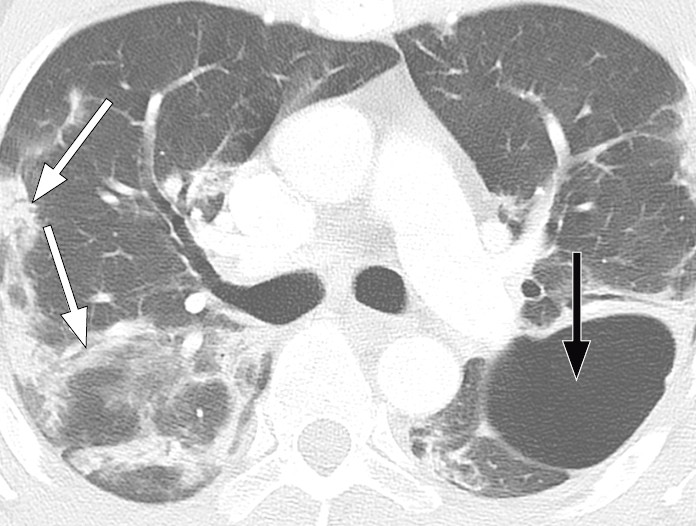

Typiske CT-funn varierer med symptomvarighet og kan deles i tre stadier: en tidlig fase, en intermediær fase som strekker seg fra 3–5 dager etter symptomdebut, og en senfase. Det er ikke alltid funn på CT de første dagene etter symptomdebut. I et materiale med symptomatiske, men uspesifiserte pasienter hadde 56 % normale funn på CT innen to dager etter symptomdebut (12), avtakende til 9 % 3–5 dager etter symptomdebut og 4 % 6–12 dager etter symptomdebut. Funnhyppighet varierer med sykdommens alvorlighetsgrad. Ved første gangs bildediagnostikk var det normale funn hos 18 % i en gruppe pasienter med ikke alvorlig sykdom, men hos bare 3 % av pasienter med alvorlig sykdom (15). Typiske CT-funn er multiple, bilaterale mattglassfortetninger med perifer distribusjon, hyppigst lokalisert i underlappene. I intermediær fase er det økende innslag av konsolidering (tette infiltrater) og affeksjon av flere lapper samt økt septering med brosteinsmønster (crazy paving) som tegn på interstitiell affeksjon. I senfasen er det økende total utbredelse, men mattglassfortetninger og konsolidering er fremdeles dominerende funn (12, 16). Figur 4, figur 5 og figur 6 viser typiske funn på CT i ulike faser av covid-19.

Ved alvorlig sykdomsforløp kan det påvises distorsjon av lungearkitekturen, traksjonsbronkiektasier, forstørrede lymfeknuter og pleuravæske. Dette er funn som ikke er spesifikke for covid-19 (17).

Hos pasienter med akutt lungesviktsyndrom (ARDS) kan CT gi nyttig informasjon om tilgjengelig, ventilerbart lungevolum for å optimalisere ventilering (31, 32), og det kan være vesentlig å avklare eventuelle bullae eller pneumothorax. Hos pasienter med bekreftet covid-19 kan CT være indisert ved mistanke om komplikasjoner som lungeembolisme eller superinfeksjon (figur 7) og i oppfølging av uavklarte funn på røntgen thorax.